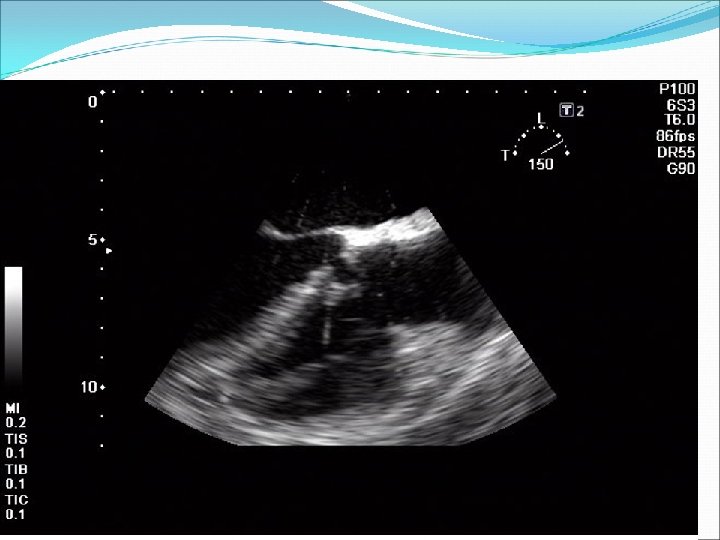

Defekt síňového septa: diagnostika echokardiografie, často jícnová: dilatovaná pravá komora zkratový proud barevným dopplerovským vyšetřením při přítomnosti trikuspidální regurgitace neinvazivně z rychlosti regurgitace odhadovat výši systolického tlaku v plicnici kalkulovat systémový průtok(Qs) ve výtokovém traktu levé komory a plicní průtok(Qp) v kmeni plicnice a počítat jejich poměr EKG: obraz bloku pravého raménka Tawarova u 95 % pacientů je projevem opožděné aktivace dilatované pravé komory Skiagram hrudníku : dilatace pravé komory, pravé síně, dilatace plicnice, zvýšenou plicní kresbu. Katetrizační vyšetření : před uzávěrem defektu u starších pacientů k posouzení plicní vaskulární rezistence a k provedení selektivní koronarografie.